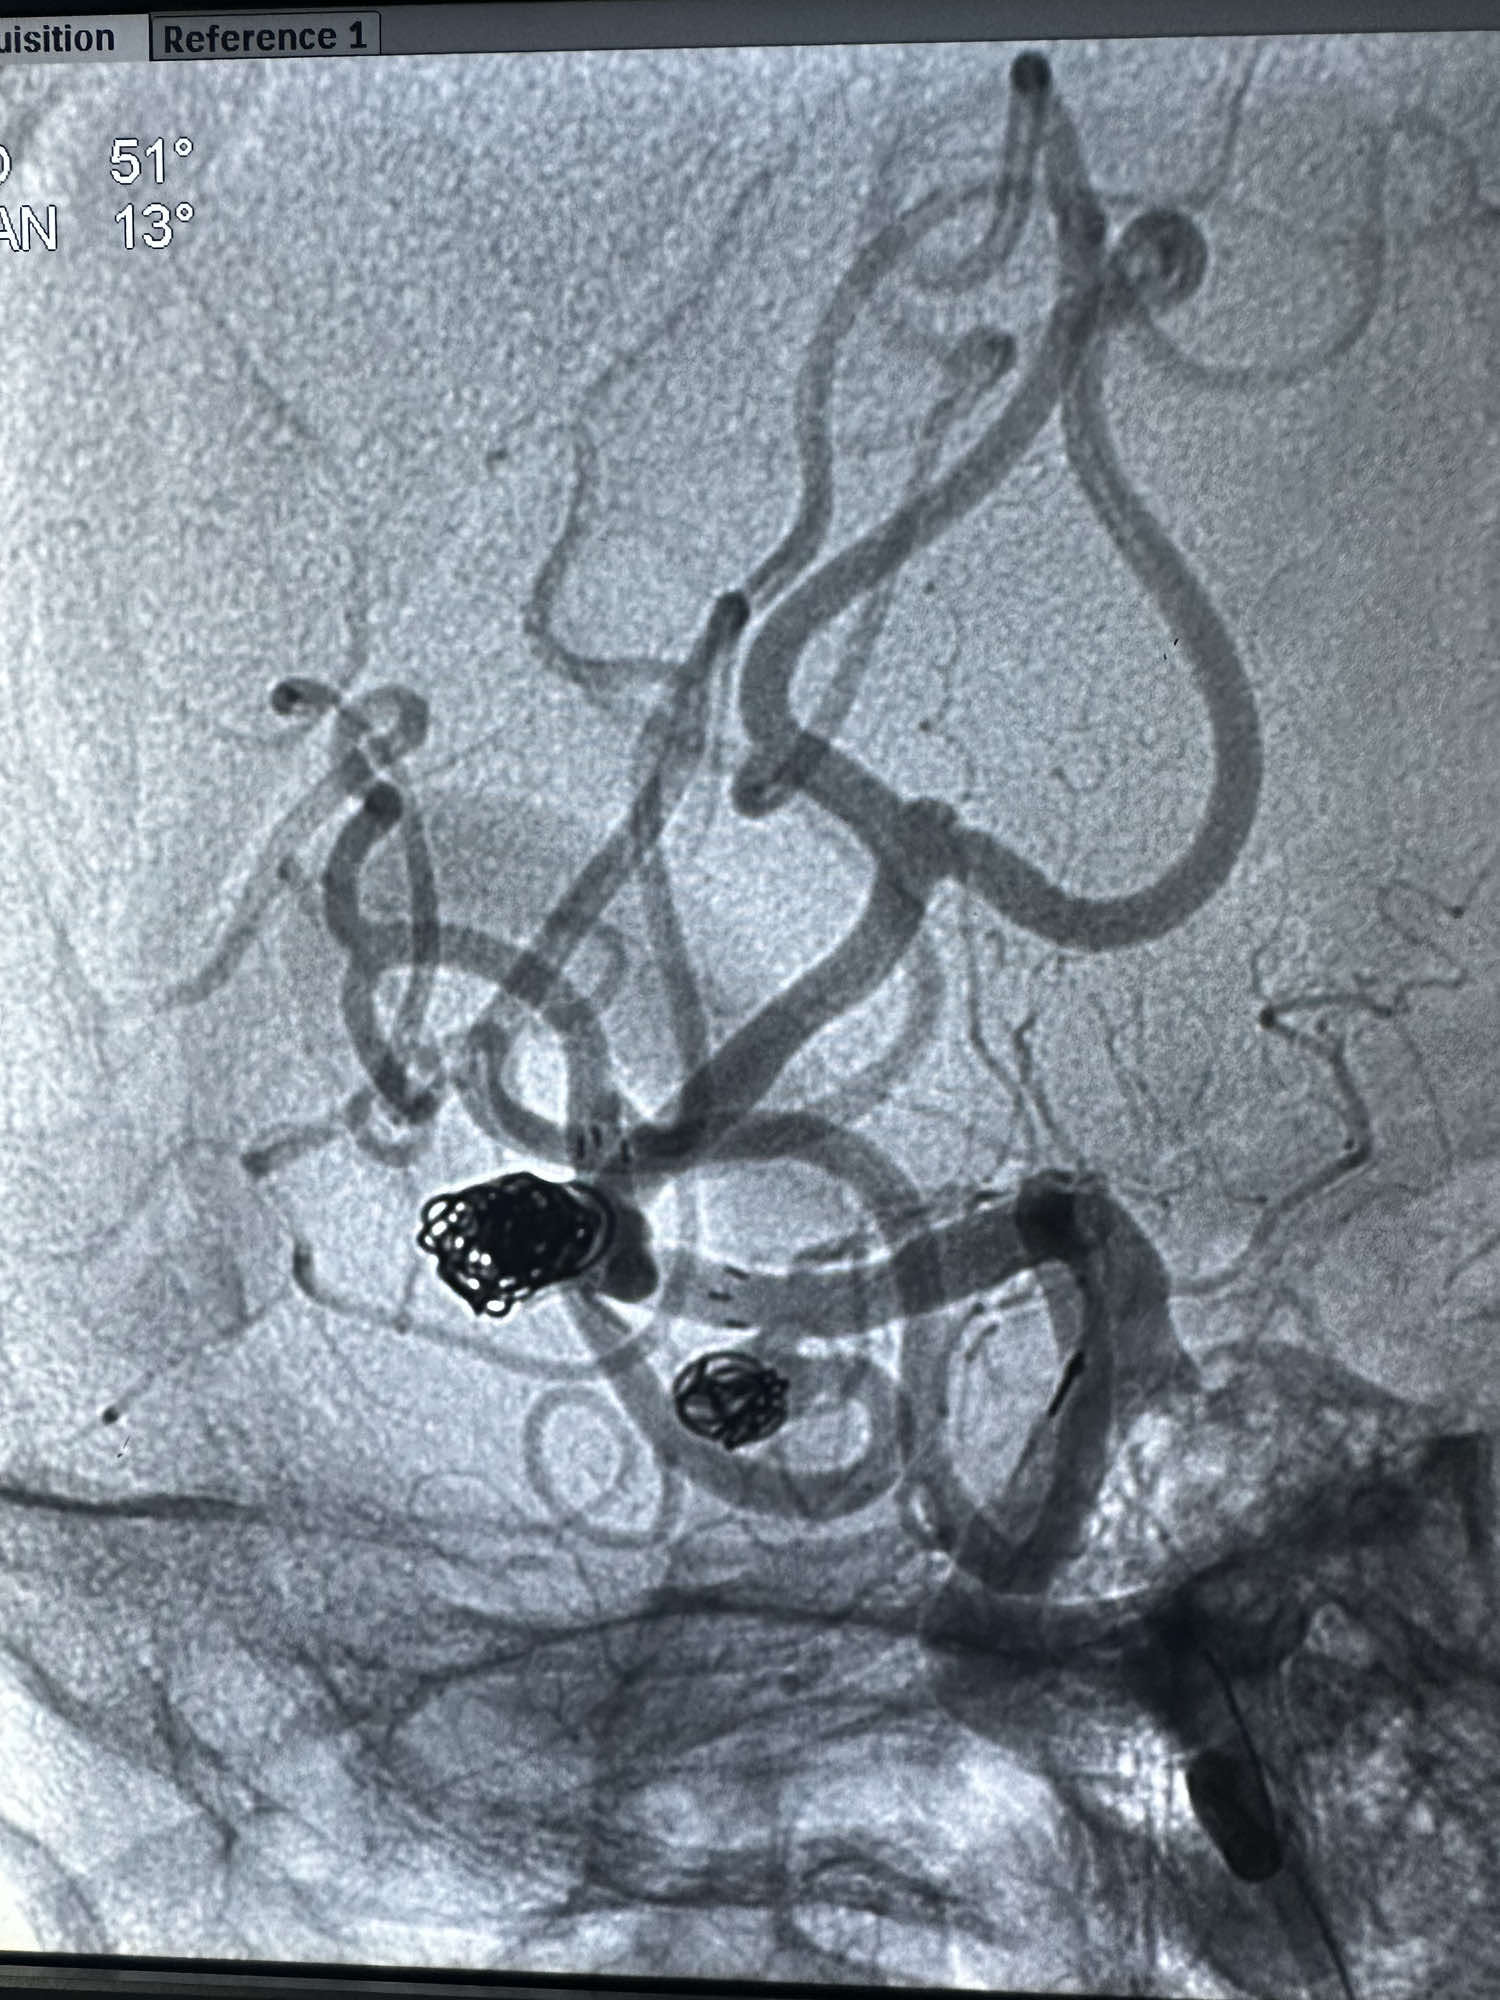

直接单纯栓塞处理,第一枚圈选择4*8的3D的弹簧圈

后续填入两枚史赛克的弹簧圈

最后骨窗的形态